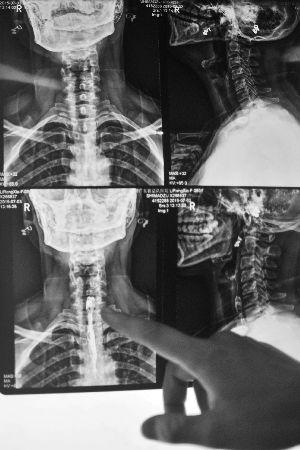

从X光片可以看见黎女士喉咙中的异物。

主治医生李靖称,患者入院时,由于喉咙红肿严重,初步检查无法判断异物位置,为安全起见,先为其做消肿治疗。“后来才知道是粽子里的枣核卡里面了,现在要等复查结果。如果异物不能顺下去,就要考虑手术治疗了。”黎女士称,目前她喉咙的疼痛感减弱不少,但喝水、吃东西还是会有明显的不适。